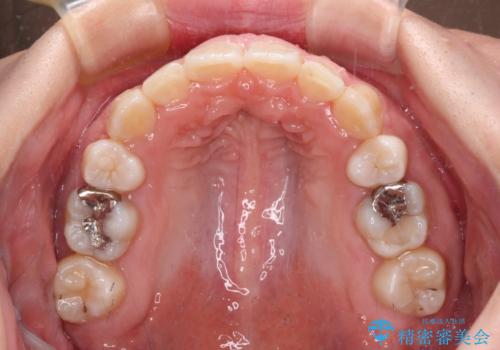

著しい八重歯を短期間で改善 ワイヤー装置による抜歯矯正

著しい過蓋咬合の改善が必要であった割には、治療期間は2年強と標準的でした。

八重歯は3,4か月で速やかに改善されました。